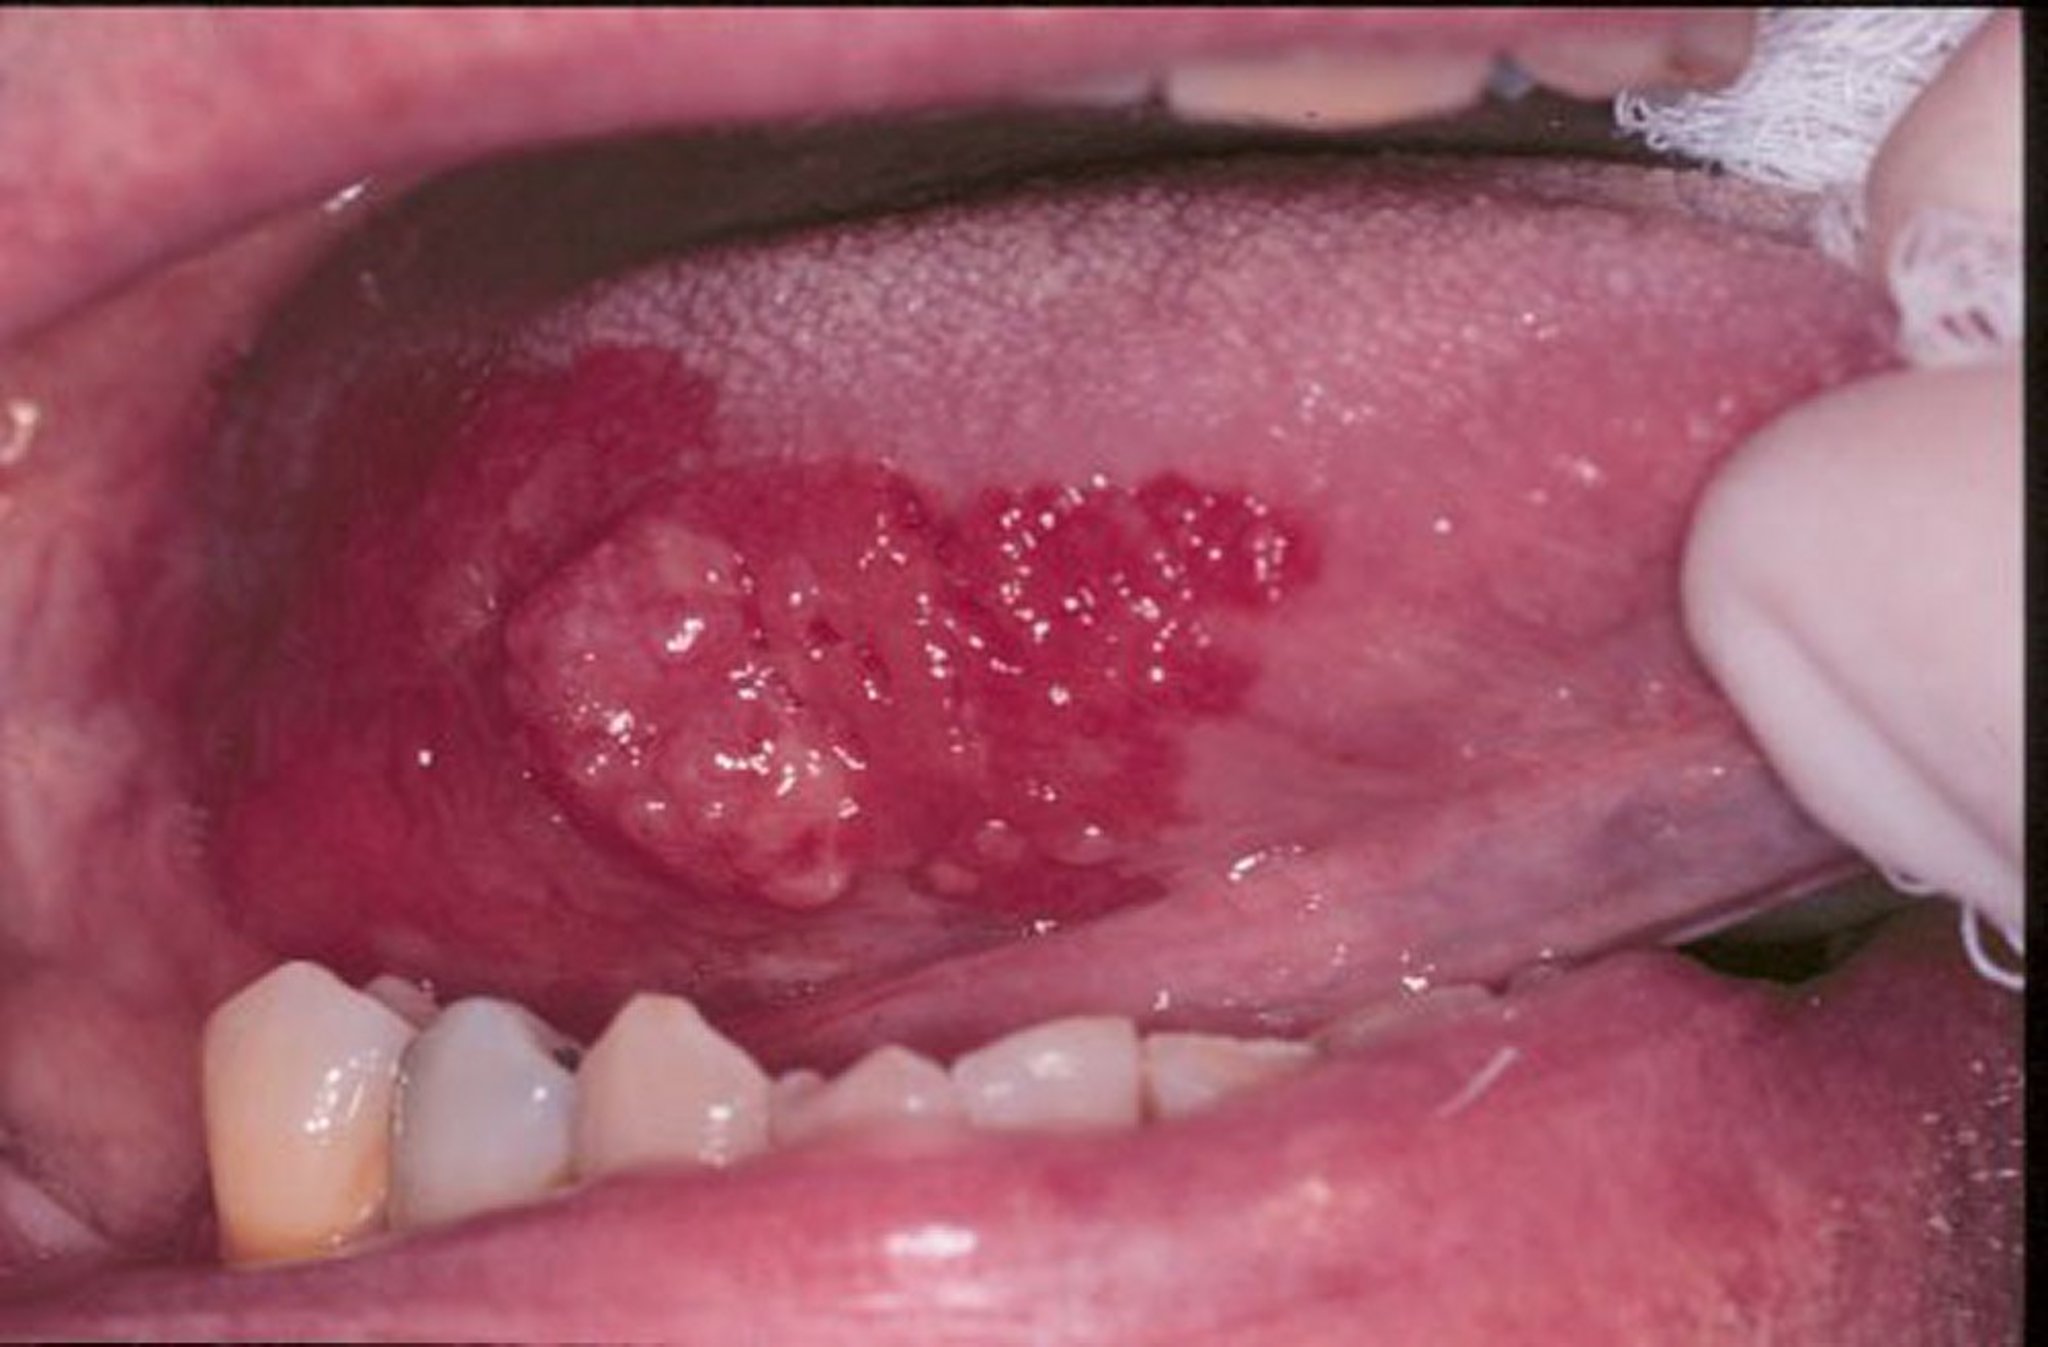

Eritroplakia adalah istilah umum untuk luka yang terlihat seperti beludru merah usang yang terjadi di mulut. Pada gambar ini, karsinoma sel skuamosa dikelilingi oleh margin eritropolakia.

Gambar disediakan oleh Jonathan A. Ship, DMD.